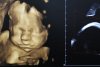

УЗИ в I триместре беременности. Часть 1

В I триместре беременности для УЗИ-диагностики тазовых и плодных структур показаны трансвагинальное и трансабдоминальное исследования, совокупность данных которых предоставляют взаимодополняющую

• УЗИ в I триместре беременности. Часть 2

УЗИ в I триместре беременности. Часть 2